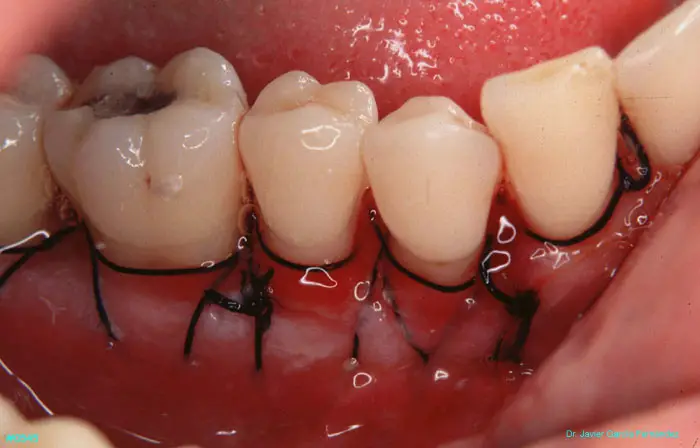

Atlas of Surgical Techniques in Periodontics. Chapter II. Atlas de Técnicas Quirúrgicas en Periodoncia